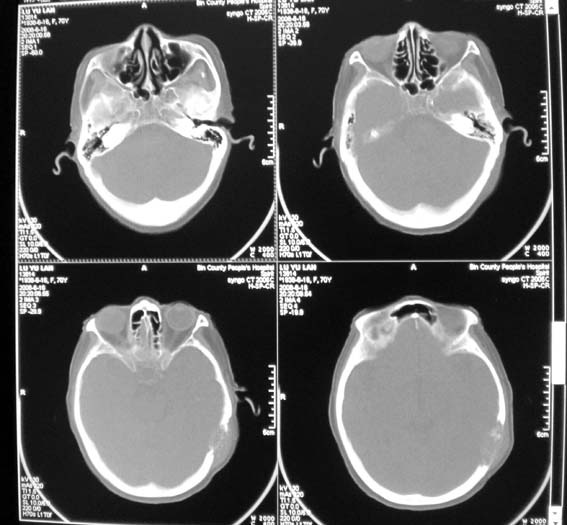

女,70岁,双肺结核,头痛,肿胀包块半年余,逐渐增大。

老年性病人,颅骨破坏首先应考虑转移瘤,还应当与颅骨嗜酸性肉芽肿鉴别

溶骨性破坏,未见明确死骨;病灶边缘不整,我考虑为颅骨转移瘤可能性大。建议仔细询问病史,积极寻找原发病灶。肺部如果扫描,最好请一并上传。

ct14067:颅骨破坏结果,转移瘤!

肝脏ct示肝癌,颅骨为转移所致!